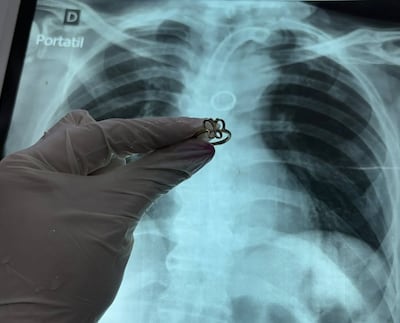

Ante la situación, los especialistas optaron por retirar la cánula traqueal e ingresar con un broncoscopio rígido por la vía oral. Finalmente, lograron ubicar y extraer el objeto.

“El anillo estaba brillando donde nunca debería estar”, describió el médico.